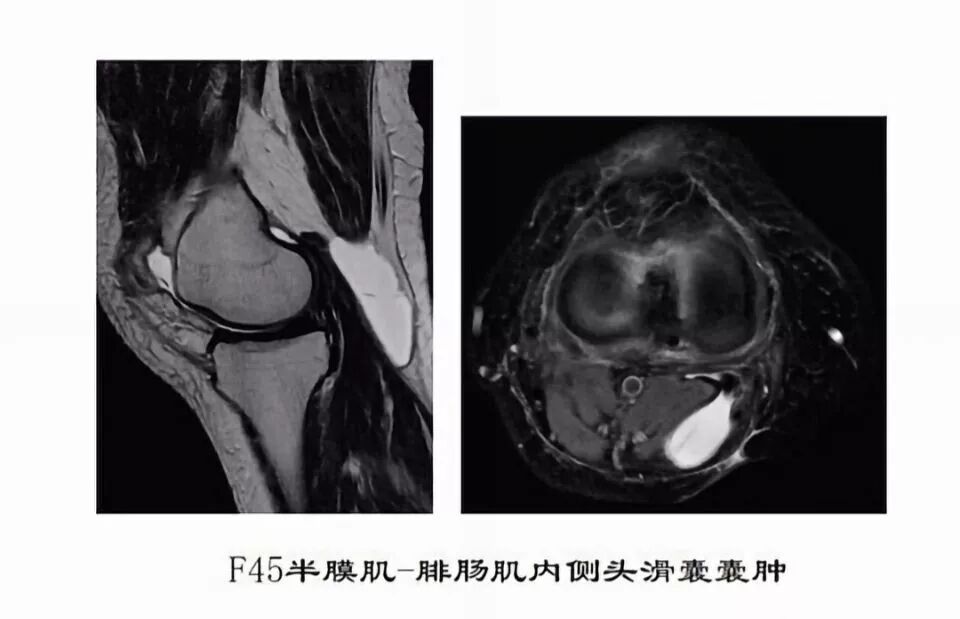

滑囊是关节囊外的囊性结构,可与关节囊相通,其作用是减少肌腱、骨和皮肤之间的摩擦。可以分为先天性滑囊和获得性滑囊。